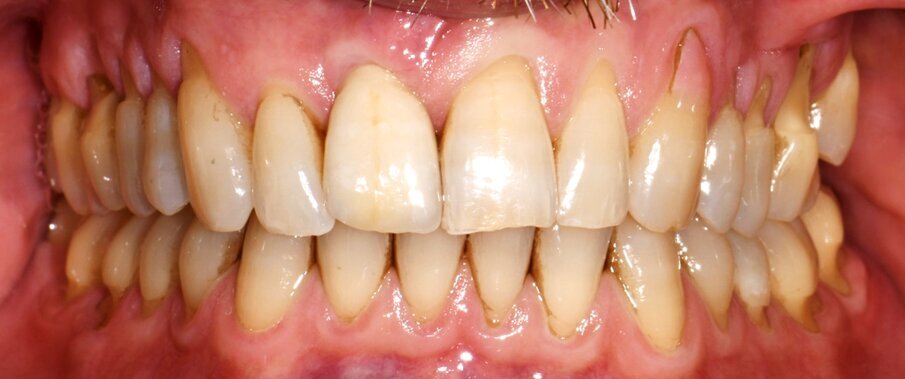

Le immagini dei controlli a 1 mese e ad 1 anno dimostravano come la tecnica MCAF con l’interposizione della matrice collagenica tridimensionale di origine equina (XC COLLAGEN Xenomatrix, Bioteck Spa) sia in grado di garantire un risultato stabile in termini di copertura radicolare (Figg. 7-10b).

Figg. 10a, 10b - Confronto tra la situazione di recessione gengivale iniziale nel secondo quadrante e ad 1 anno di follow-up. Si noti l’ispessimento dei tessuti molli e l’ottima copertura radicolare raggiunta.